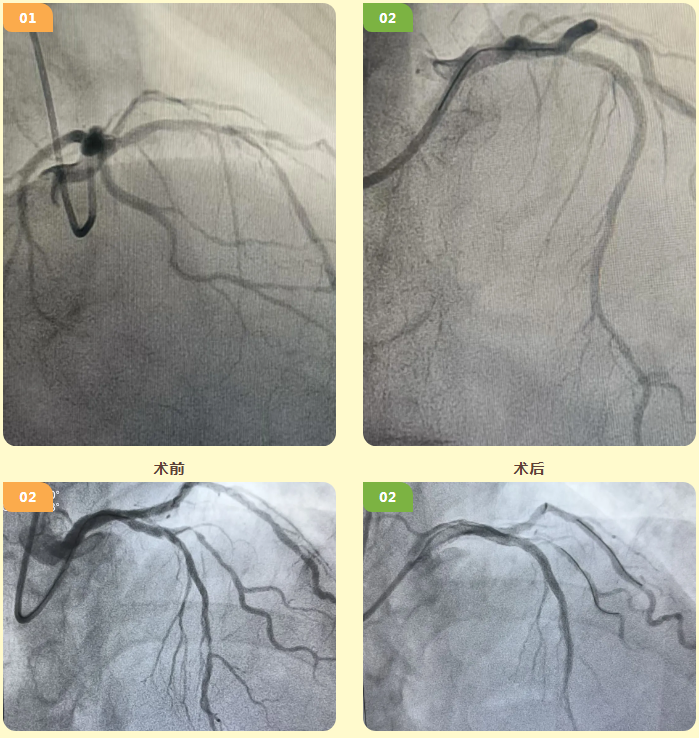

58岁患者有多年糖尿病、高血压病史,近期因反复胸痛入院。冠脉造影提示,其LAD冠状动脉全程严重钙化并伴狭窄,常规导丝无法顺利通过,手术难度大。

56岁的患者患有高血压,且有长期吸烟史,近期同样因反复胸痛就诊。冠脉造影显示,其LAD冠状动脉近中段严重钙化伴狭窄,普通球囊扩张效果不佳,常规介入治疗难以实施。

另一位72岁的患者则因反复活动后胸闷入院,冠脉造影提示LAD冠状动脉中远段严重钙化伴狭窄,需针对性制定治疗方案。

针对三位患者的复杂病情,心病科专家团队经充分研讨评估,均决定采用冠状动脉旋磨术。术中,专家团队采用各个型号磨头分阶段旋磨钙化段,待钙化斑块充分消融后,顺利植入支架,患者冠脉血流均恢复至TIMI 3级。

心病科毛艳阳主任说:“此次接受治疗的患者均为弥漫性重度冠脉钙化病变,其中一例更是面临前降支近端360度环形钙化的复杂情况,手术难度极高。心病科手术团队秉持严谨专业的态度,术前结合冠脉IVUS(血管内超声)进行精准评估,量身制定个性化手术方案;术中凭借精湛技术开展精细化操作,为患者顺利实现血管再通。术后,患者胸痛症状均缓解,恢复情况良好,目前已顺利康复出院,重返正常生活。”